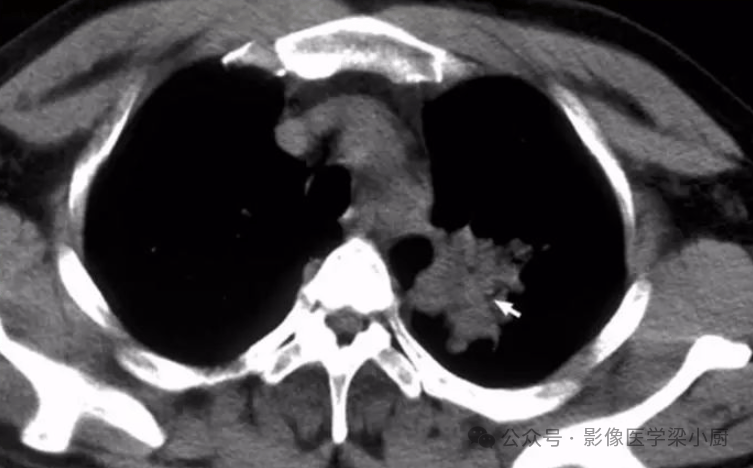

案例 2:右肺中下叶开口肿瘤(无痛气管镜下电圈套器切除)

患者情况:中年女性,因胸闷、气促就诊,胸部 CT 示右肺中下叶开口肿瘤,阻塞气道导致肺通气功能下降,需明确肿瘤性质并缓解梗阻症状。

手术操作:采用无痛气管镜技术,将电圈套器通过镜体工作通道送至肿瘤位置,调整圈套环完全包裹肿瘤,完整取出肿瘤组织,同时收集标本送检病理。

治疗效果:手术仅用 20 分钟,术中无明显出血,患者术后生命体征平稳,气道梗阻症状即时缓解,病理结果为低分化腺癌,为后续化疗方案制定提供依据,术后 2 周可正常活动。